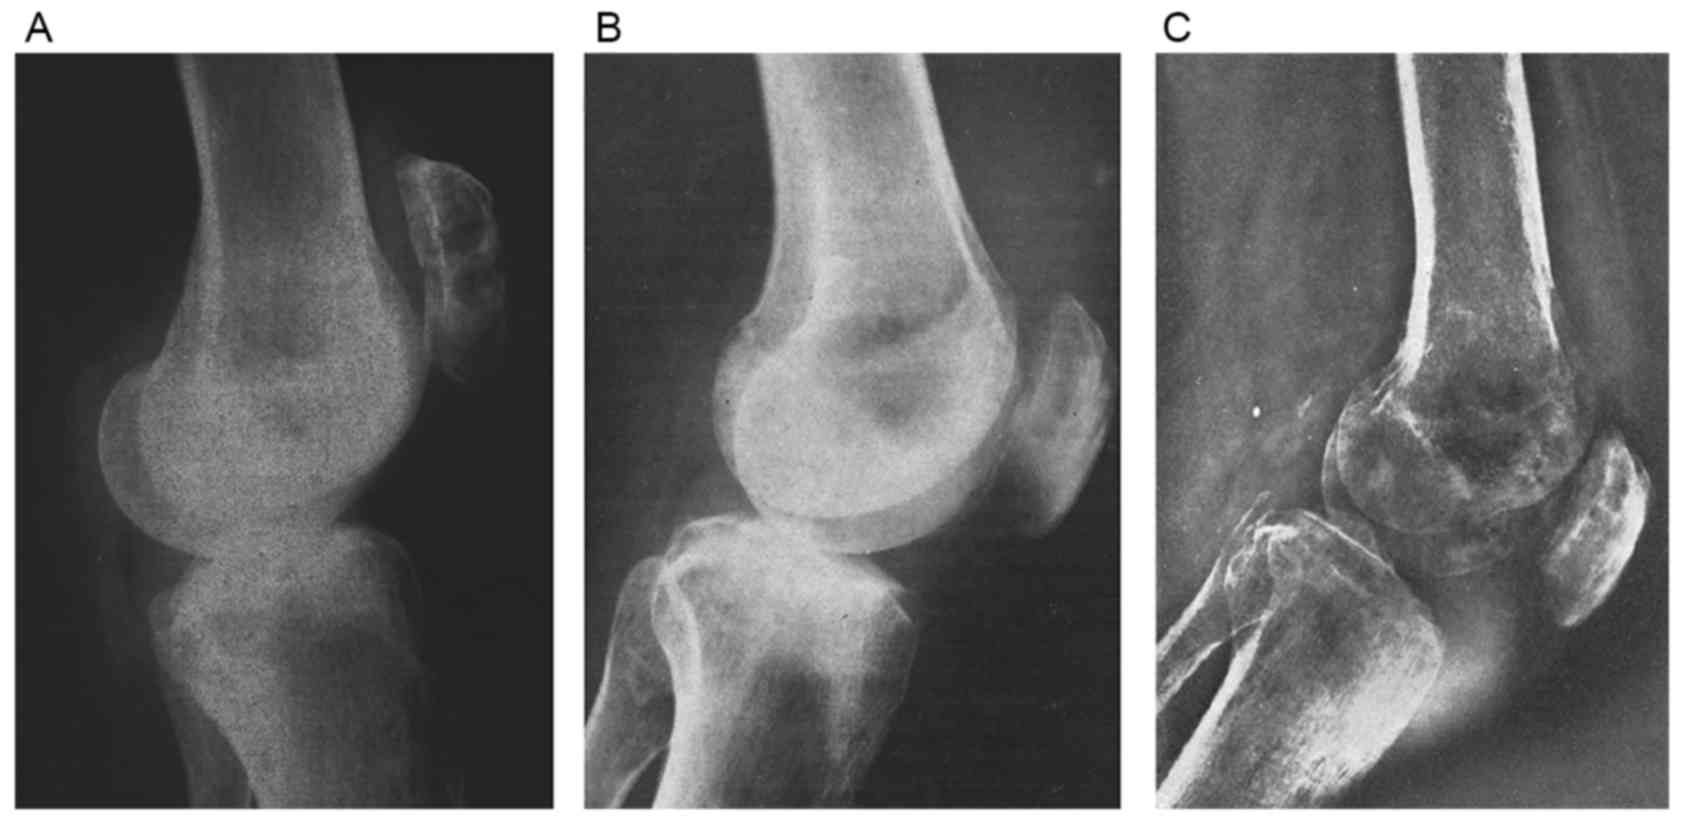

Patellar metastasis from primary tumor (Review)

Although bone tumors are frequently located in the knee area, primary tumors of the patella are rare and patellar metastases are even rarer. Knee pain is the most common complaint of patients with patellar metastases. Owing to the low incidence of patellar metastases, misdiagnosis is not unusual. The present review analyzes ~44 cases of patellar metastases originating from distinct primary sites. Reports of malignant tumors of the lung and kidney metastasizing to the patella were more common than those of other patellar metastases. Relative incidence, symptomatology, imaging features, histopathology and treatment options for these patellar metastatic lesions are described respectively along with a review of the literature. Despite numerous experiments demonstrating the reasons for implantation of tumor in patella, the answer to this question has not yet been revealed. In the light of the increasing attention on the diagnosis and the treatment of these lesions, the availability of the integrated information regarding metastases in the patella becomes more relevant.

Figure 3